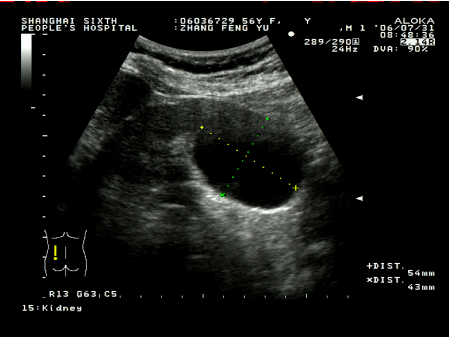

超聲引導下腎囊腫穿刺硬化治療具有簡單易行,患者少痛苦,復發率低,費用低等優點。這種方法是用超聲診斷儀事先選定穿刺點,設計好進針角度和進針深度,在局部麻醉下,用專用的穿刺探頭,根據已設定的角度和深度把直徑0.8毫米或1.2毫米的針插入囊腫,因為囊腫、針道和周圍臟器全部在超聲屏幕上看到,所以不會損傷周圍臟器,待抽凈囊液后,注入硬化劑,使硬化劑與囊腫內壁上皮接觸,達到硬化效果,數分鐘后把硬化劑抽出,拔出穿刺針,整個治療過程安全。在硬化治療后的早期(一個月內),一般說,囊腫上皮因硬化劑燒灼作用,會有滲出,一個月后開始漸漸吸收,三個月后明顯縮小,直至囊腫完全消失。

術前囊腫大小50mm左右